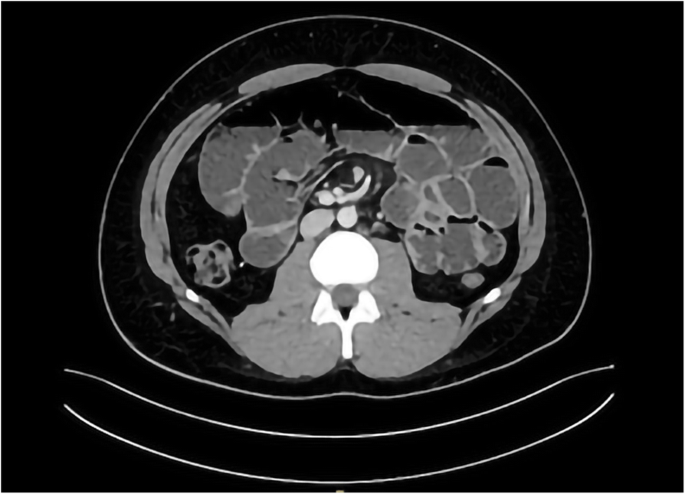

A subsequent abdominal computed tomography (CT) scan with intravenous contrast confirmed the small bowel distension with air-fluid levels, and showed a reduction in distal ileum diameter in the right iliac fossa with an empty marbled colon. No obvious causes of mechanical SBO came to light. (Fig. 2).